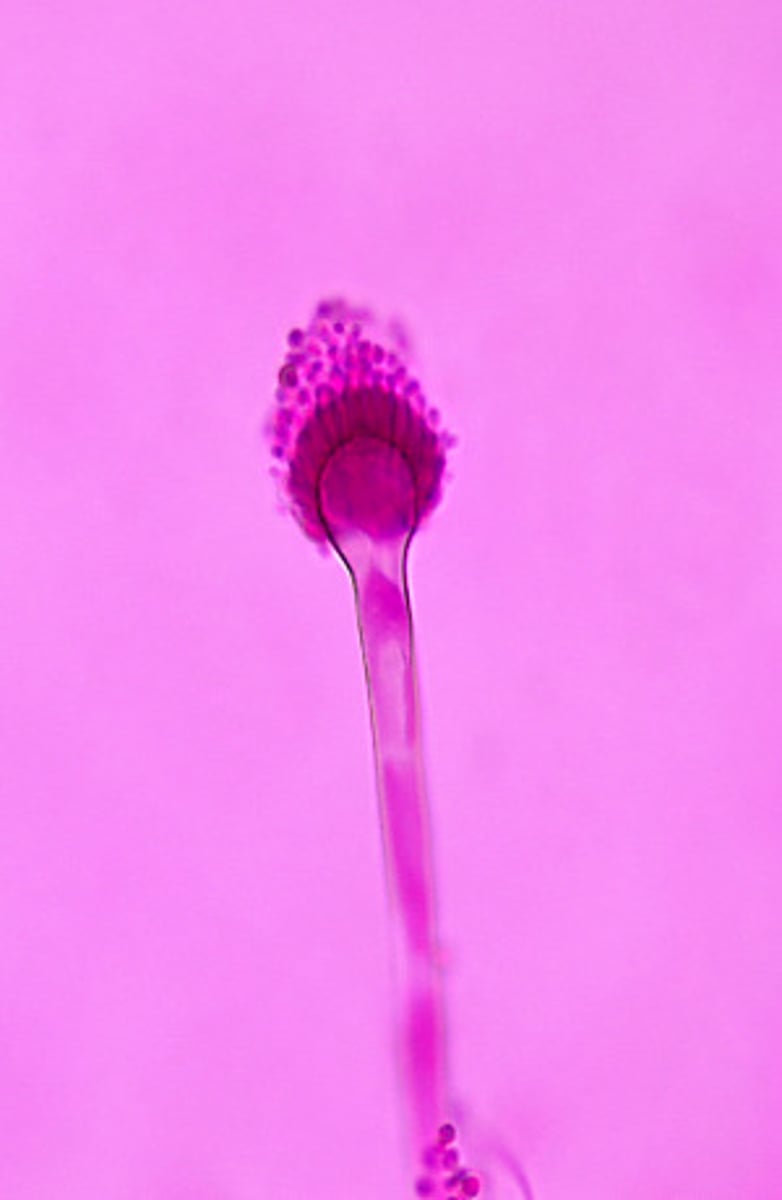

This microscopic image suggests which of the following molds?

Rhizopus spp. produce sporanigia borne on long sporanigiophores. Rhizoids are produced directly opposite the sporangiophore.